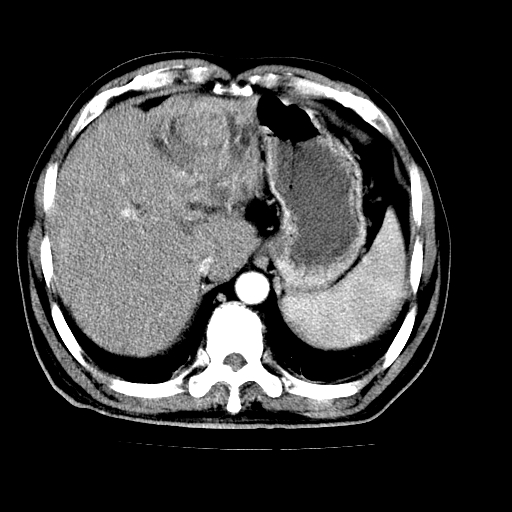

男,66岁,上腹部不适、黄染一周。彩超示:肝左叶占位,肝内胆管扩张,胆总管扩张,胆总管占位?

肝左叶不规则软组织肿块影,边缘不规整邻近肝实质受累分界不清;肝内胆管(左叶)明显扩张成“软藤状”,诊断:肝左叶胆管细胞癌。

肝左叶占位性病变,并胆管扩张,符合胆管细胞癌ct表现,门脉左支受累,左肾囊肿。窗宽太窄了,其他的看不清

左叶胆管细胞癌累及胆总管,门脉左支受侵,慢性胆囊炎胆结石,左肾小囊肿

肝左叶不规则软组织肿块影,边缘不规整邻近肝实质受累分界不清;肝内胆管(左叶)明显扩张成“软藤状”,诊断:肝左叶胆管细胞癌。胆囊钙乳症。